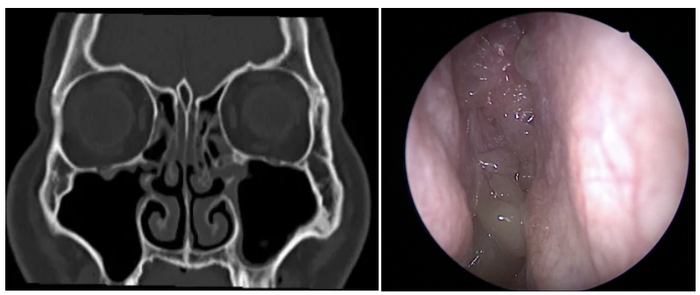

赖婶是位身材瘦小的老年人,多年来一直受到双耳鸣的折磨,尽管她就诊于各大医院,但每次检查均显示听力正常。于是,赖婶慕名来到刘教授的门诊。

经检查,赖婶的耳膜略有内陷,虽然她中耳压力监测(声导抗检查)显示正常,然而,赖婶反馈,每次做这个检查后,症状会有所缓解。为了进一步诊断,刘教授为赖婶进行了电子鼻咽镜检查。结果显示,赖婶的鼻腔内存在较多鼻息肉,部分鼻息肉甚至突向鼻咽部,并伴有脓性分泌物,鼻窦CT扫描则提示存在双侧全组鼻窦炎。综合以上检查结果,刘教授诊断赖婶患有双侧咽鼓管功能紊乱,双慢性鼻-鼻窦炎伴鼻息肉。

针对该诊断,刘教授为赖婶制定了治疗方案:先行双侧鼻内镜鼻窦手术,术后继续药物治疗;待鼻息肉得到控制后,观察耳鸣情况有无改善,若仍有耳鸣,再考虑进行咽鼓管球囊扩张术。赖婶接受了刘教授的建议,接受了鼻内镜手术。术后半年,赖婶暂时没有耳鸣状况,她非常开心。